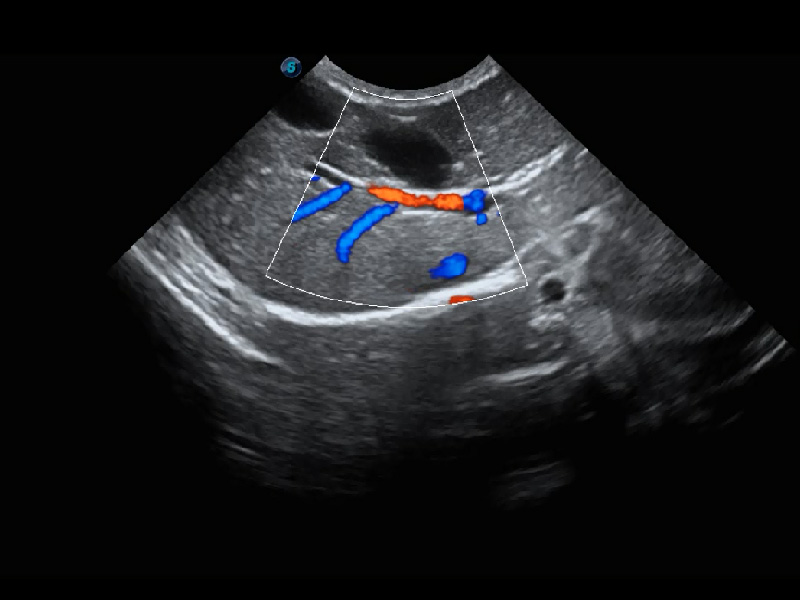

ProPet 60 作为一款高端台式动物超声设备,为动物医生的日常诊断提供了一系列贴合动物临床需求、解决临床实际问题的高级成像功能。凭借全系列高清探头,满足医生对腹部、心脏、生殖、浅表、肌骨等成像的所有需求,切实帮助您提升检查效率,提高诊断信心。

动物是人类最亲密的朋友和最值得信赖的伙伴。亚星官网也一直致力于探索动物专用的超声影像解决方案。 全新推出的ProPet系列,是亚星官网在动物超声影像智能化、专业化、精准化的一次跨越式革新。动物不能用言语来表述自己的不适,通过超声影像,ProPet系列搭建了动物医生与不同物种沟通的“桥梁”,为动物医生注入了“治愈之力”。